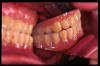

CM Edentulismo parcial, restos radiculares y caries